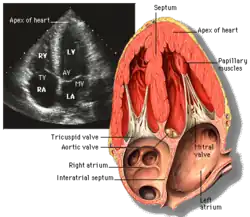

Subcostal four chamber |

Apical four chamber |

| Each figure contains a TTE with a black background, and a corresponding colored illustration. | Patrick J. Lynch and C. Carl Jaffe, Yale University, 2006. | ||||||||||

| Click on a figure to enlarge it and see some parts of the heart identified. RV, right ventricle; LV, left ventricle; RA, right atrium; LA, left atrium; TV, tricuspid valve; MV, mitral valve; AV, aortic valve; RVOT, right ventricular outflow tract; LVOT, left ventricular outflow tract | |||||||||||